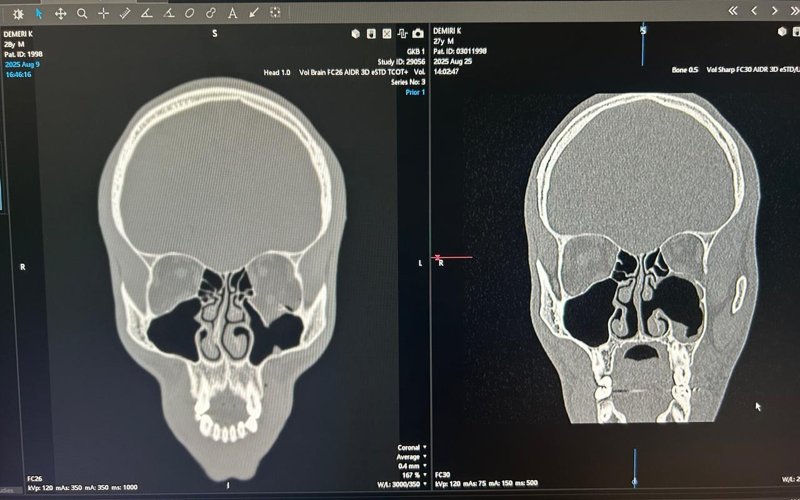

— Пострадавший был доставлен в городскую клиническую больницу № 1. У пациента диагностированы закрытый перелом костей наружного носа, смещенный перелом орбитальной стенки левой гайморовой пазухи, а также травму с пролабированием мягких тканей глазного яблока в гайморову пазуху. Его госпитализировали в ЛОР-отделение, где хирурги выполнили репозицию костных отломков и эндоскопическую баллонопластику, — рассказали врачи.